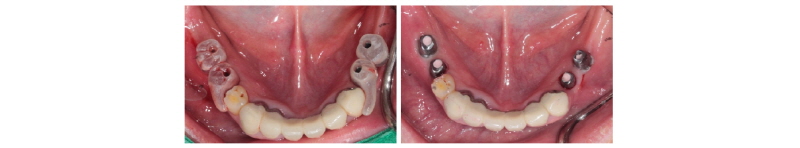

본 59세 여환은 양쪽 위, 아래 큰 어금니가 흔들리고 잇몸이 부었으며 왼쪽 아래 큰 어금니는 오랫동안 없었다는 주소로 본원에 내원하여 임상 및 방사선학적 검진 결과 아래와 같이 관찰되었다. #33 치아는 Mob (+++) Per (+)와 bone loss, #16, 26, 46 치아는 Mob (++/+++) Per (+)와 bone loss, #36, 37 치아는 missing 상태였다. 이에 #16, 26, 33, 46 치아는 hopeless teeth, #17, 36, 37, 47 치아는 missing teeth로 진단되었다(Fig. 19). #16, 26, 33, 46 치아는 발치 후, #i16, i17, i26, i33, i36, i37, i46, i47에 implant 식립과 #i16, i17, i26에 sinus lifting 및 #i33, i46, i47에 GBR을 계획하였다. #i36, i37은 flapless implant surgery 및 immediate loading을 계획하였다. #16, 26, 33, 46 치아를 발치하였고, 2개월 후에, 상, 하 rubber impression 채득 후, stone model 제작하였다. 또한 arch 전용 tray를 bite한 상태로(Fig. 20, 21) CBCT 촬영을 하였다(PHT-30LFO, VATECH). 이후 CBCT 영상과 alveolar ridge와 soft tissue model을 scanning한 영상(TRANSFORMER, Megagen)을 정합하였다. 새로운 영상을 바탕으로 #i36, i37 위치에 implant fixture 식립과 customized abutment와 provisional bridge를 design하였다(R2GATETM, Megagen, Fig. 22, 23). Design대로 3D printer (Perfactory Digital Dental Printer 3, EnvisionTEC) 통해 surgical guide를 제작하였고(Fig. 24) milling machine (TicamPro and WhitecamPro, Megagen)으로 customized abutment와 provisional bridge를 milling하였다(Fig. 28). 임플란트 수술은 5회에 걸쳐서 진행하기로 하였다. 첫 번째 수술일에는 #i36, i37 fixture 식립과 동시에 abutment 체결과 provisional bridge를 합착하였다(Fig. 25-27, 29). 이후, 1개월 후에 #i16, i17 fixture 식립과 lateral approach로써 sinus lifting을 시술하였다. 3개월 후에 #i36, i37에 최종 인상 채득하여 도재금관 수복을 하였다(Fig. 30, 31). 향후 남은 부위에 임플란트 수술 및 보철 진행 예정이다.

Fig. 29. Customized Titanium abutments were connected on #i36, i37. |

Fig. 30. PFM bridge (final prosthesis) was cemented on #i36, i37. |

Fig. 31. Periapical radiograph on #i36, i37 after final prosthesis. |